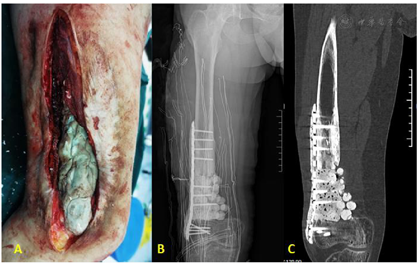

第2阶段在第1次手术8周后进行。根据以下标准评估感染是否控制:(1)全身无发热表现,患者精神状况及感觉良好。(2)手术部位及周围无感染体征:伤口愈合良好、无疼痛、发红、渗出或脓液等。(3)实验室指标正常:包括红细胞沉降率(ESR)、C反应蛋白(CRP)、降钙素原(PCT)和白细胞(WBC)计数正常。如果同时达到上述指标,则认为感染控制,予二期手术重建。在原切口处切开,纵向切开诱导膜(图4A)。然后在抗生素水泥涂层的锁定钢板上剥离覆盖的骨水泥,去除骨蜡暴露螺钉并将钢板螺丝钉及骨水泥完全取出(图4B);彻底冲洗,更换长股骨远端外侧钢板,远近端各打入螺丝钉固定,并辅助可延长单边外固定架固定,在股骨中上段用微型截骨器截骨(图4C,图4D),截骨后通过单边外固定架搬移骨块(每天1mm,分3-4次进行),待断端会师后,再次切开伤口会师部分,在原钢板上通过电钻钻孔,植入2枚锁定螺丝钉固定搬移骨块,会师端取自体髂骨植入,等待骨质矿化及愈合(图4E,图4F,图4G,图4H)。

通过治疗,患者感染得到控制,搬移骨端新生骨质形成,逐渐矿化,远端会师端逐渐愈合,新生骨痂形成。随访时间半年,患者感染得到控制,骨搬移端成骨良好,会师端有骨痂形成,临床治愈(图5)。